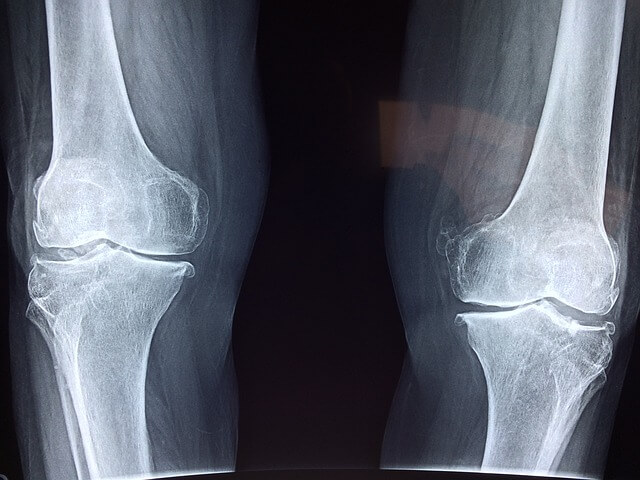

콘드로이친(Chondroitin)은 관절 건강을 지원하는 보충제로 널리 사용되고 있습니다. 많은 사람들이 관절염 및 기타 관절 질환의 증상을 완화하기 위해 콘드로이친을 섭취하지만, 모든 보충제와 마찬가지로 부작용이 발생할 수 있습니다. 콘드로이친의 잠재적인 부작용과 주의사항에 대해 알아보겠습니다.